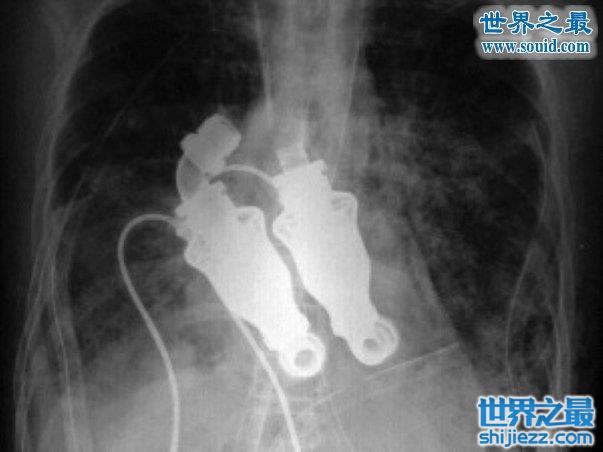

这个男人在没有心脏的情况下,依然活着。因为医学的发明让他重新生存。

来自德克萨斯心脏研究所的比利科恩博士和弗雷泽博士参加了摘除心脏的第一步。他们设计出一个装置,称之为“连续流动装置”。

在此之前,他们已经将这个装置在牛身上测试过。

之后他们将这个装置安在这位患者身上,奇迹的是,这个男人在一天内很好的活了下来。

你可能认为这个事情很怪异,但是最怪异的是这个装置能够将血液供应到身体任何一个部分,但不像心脏那样跳动,真是个奇迹。